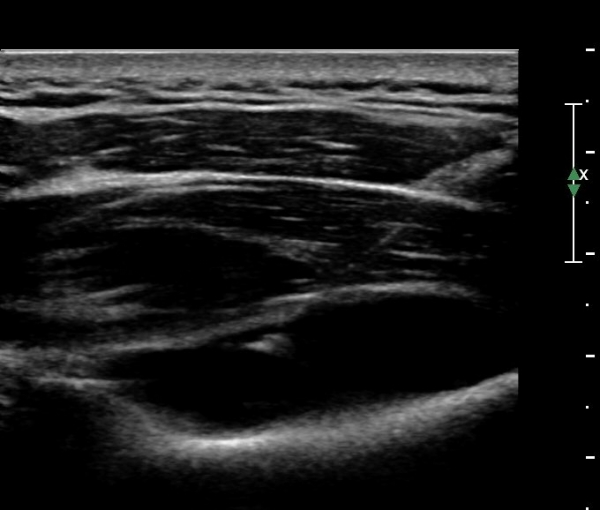

¾î±ú µÚÂÊ È¾´Ü¸é°Ë»ç¿¡¼­ °üÀý¿Í(glenoid) ³»Ãø¿¡¼­ ¸¹Àº ¾çÀÇ ¼ö¾×Àú·ù°¡ °üÂûµÈ´Ù(»çÁø 1, 2).

ÃÊÀ½ÆÄÀ¯µµÇÏ ÈíÀÎÄ¡·á Áß ÁÖ»ç¹Ù´ÃÀÌ ¼ö¾×³»¿¡ Á¤È®È÷ À§Ä¡ ÇÑ °ÍÀÌ °üÂûµÈ´Ù(»çÁø 7).

ÃÊÀ½ÆÄÀ¯µµÇÏ ÈíÀÎÄ¡·á ÈÄ ´ëºÎºÐÀÇ ¼ö¾×ÀÌ Á¦°Å µÈ °ÍÀÌ È®ÀεȴÙ(»çÁø 8).